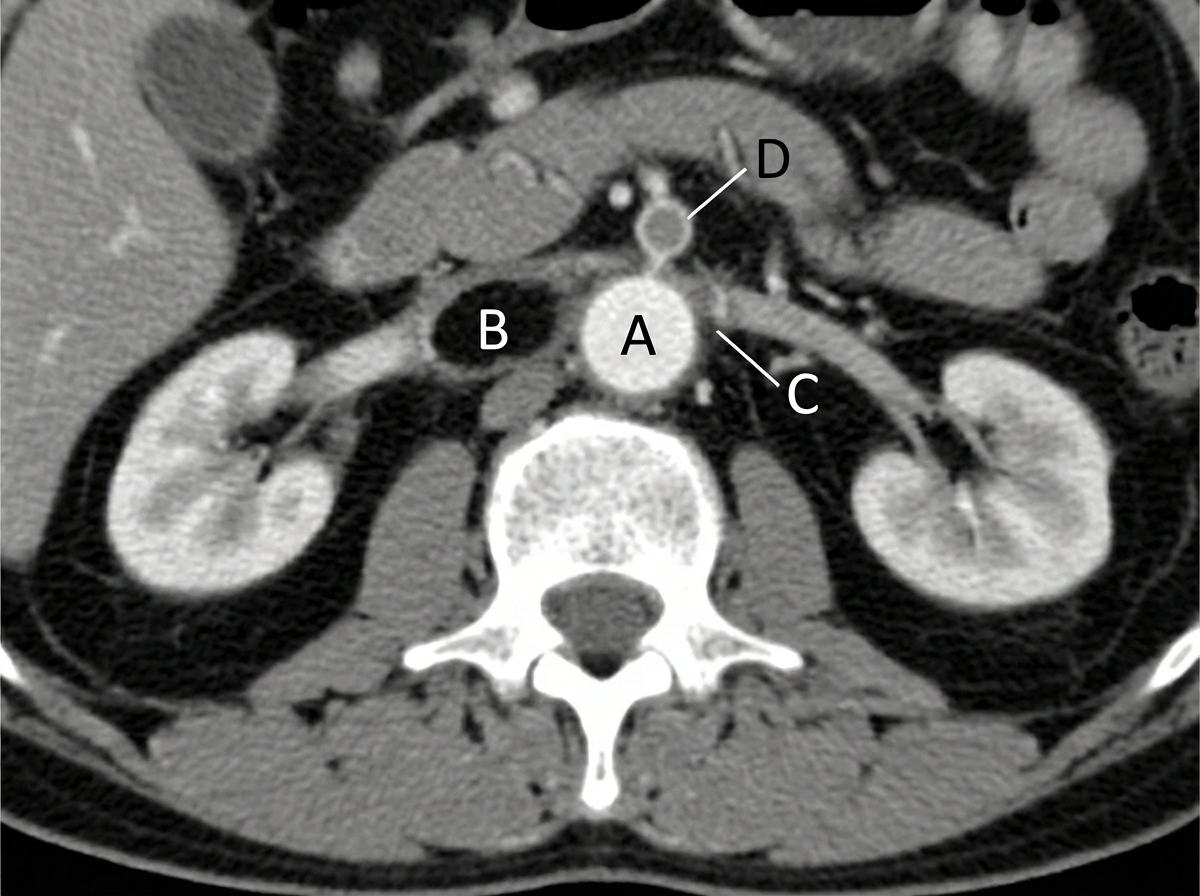

A 70-year-old woman with a history of myocardial ischemia and peripheral vascular disease presented with sudden onset of severe, rapidly increasing epigastric pain, nausea, vomiting, and minimal abdominal tenderness. She was writhing in pain, had normal bowel sounds, and a small amount of blood in her stool. Electrolyte analysis revealed a bicarbonate level of 15 mEq/L, and serum lactate was elevated, indicating tissue hypoxia and injury. A CT scan was planned. What anatomical structure is likely involved?

Explanation: ***C (Superior Mesenteric Artery)*** - The **pain out of proportion to physical findings** with **elevated lactate** and **metabolic acidosis** (bicarbonate 15 mEq/L) are classic for **acute mesenteric ischemia** affecting the SMA territory. - Patient's history of **myocardial ischemia** and **peripheral vascular disease** are significant risk factors for **mesenteric arterial thrombosis** or embolism, with the SMA being most commonly affected due to its anatomy and flow characteristics. *A (Celiac Artery)* - Celiac artery occlusion typically causes **chronic mesenteric ischemia** with **postprandial pain** and **weight loss**, not acute presentation. - The **extensive collateral circulation** from the celiac trunk usually prevents acute ischemic symptoms unless there's concurrent SMA involvement. *B (Inferior Mesenteric Artery)* - IMA territory ischemia rarely presents with **severe acute symptoms** due to **abundant collateral circulation** from the middle colic and internal iliac arteries. - **Left-sided colonic ischemia** from IMA involvement typically presents with **left lower quadrant pain** and **bloody diarrhea**, not epigastric pain. *D (Portal Vein)* - **Portal vein thrombosis** presents with **gradual onset** of **ascites**, **splenomegaly**, and **variceal bleeding**, not acute severe abdominal pain. - **Elevated lactate** and **metabolic acidosis** are uncommon in portal vein thrombosis unless there's concurrent **bowel infarction** from arterial compromise.